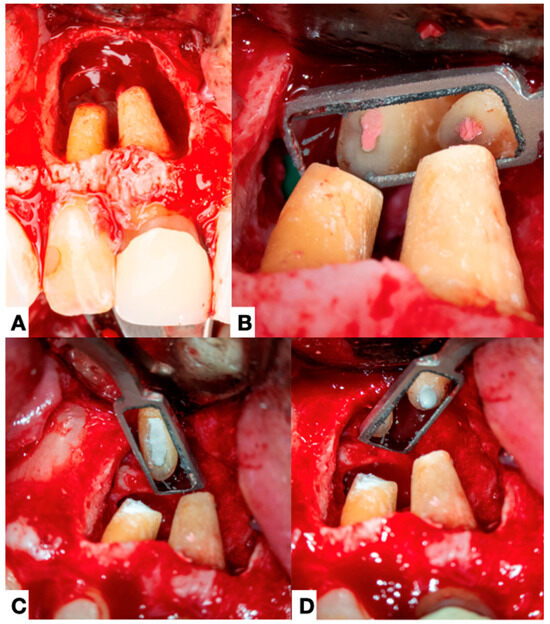

3.1.4. Extraradicular Biofilm and Calculus Formation

4.4. Treatment of the Extraradicular Infection